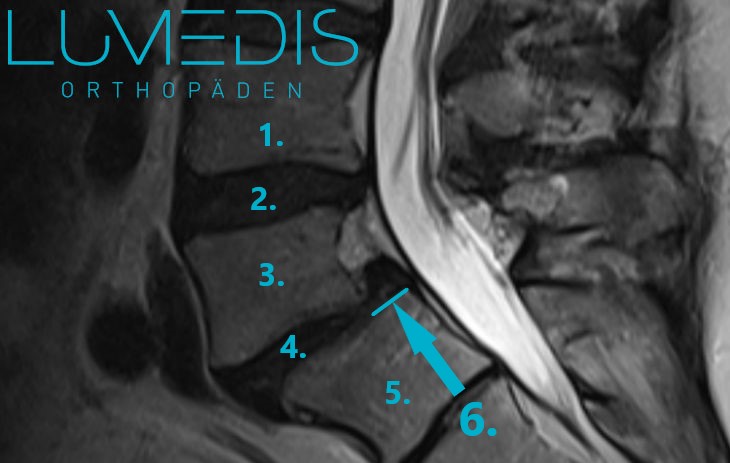

MRT der LWS T2 seitlich mit Gleitwirbel L5/S1

MRT der LWS mit Gleitwirbel L5/S1

Schematisch haben wir über die türkisen Linien aus Ausmaß des Gleitwirbels veranschaulicht (Meyerding 1).

MRT der LWS mit Gleitwirbel L5/S1 Meyerding 1

MRT Bild der LWS seitlich T2:

Man erkennt ein deutliches Wirbelgleiten (Meyerding 1) zwischen L4 und L5 und eine Spinalkanalstenose der LWS L4/5 (roter Pfeil).